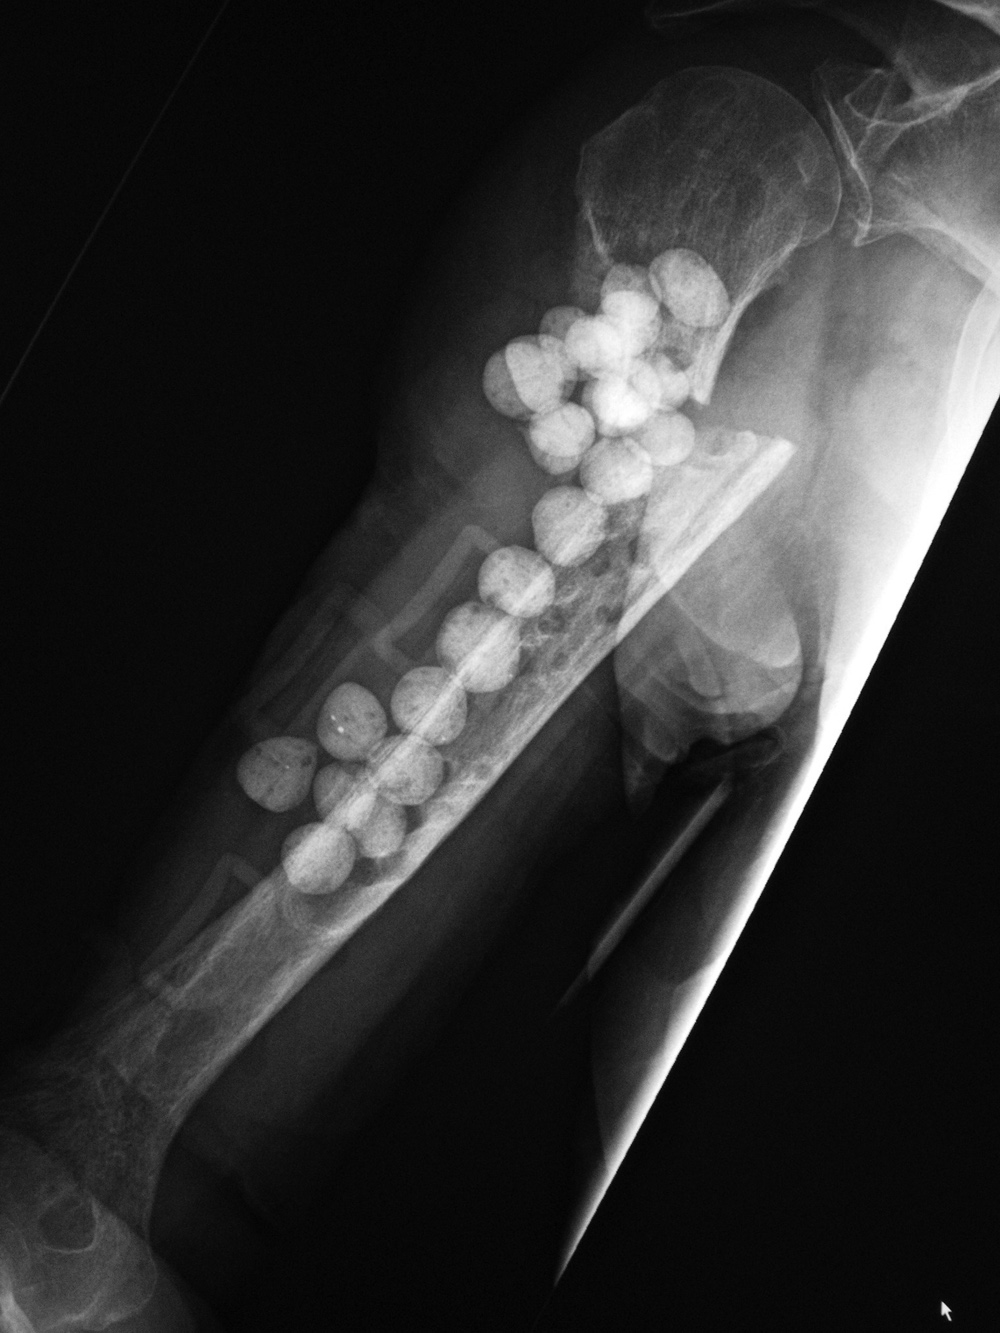

For infected fracture sites as well as for treatment of bone infections, antibiotic beads and antibiotic spacers or antibiotic rods are frequently used. The beads, spacers, and rods are typically composed of polymethyl methacrylate cement containing an antibiotic which diffuses locally into the infected bone when the beads, spacers, or rods are packed into the region of infection. The bead packing cement material also provides mechanical support in areas of missing or weakened bone (figure: antibiotic beads). Cement impregnated antibiotic spacers and antibiotic paste are used mainly after resection of infected joint arthroplasty sites. Antibiotic impregnated calcium sulfate pellets are also used in the treatment of osteomyelitis (Sherry, 2001).

The antibiotic laden cement beads were placed in an area of infected bone after removal of a infected fixation plate.

The antibiotic laden cement beads were placed in an area of infected bone after an open fracture. A periarticular locking plate is in the distal femur, and a buttress plate and interfragmentary screws are in the tibia.